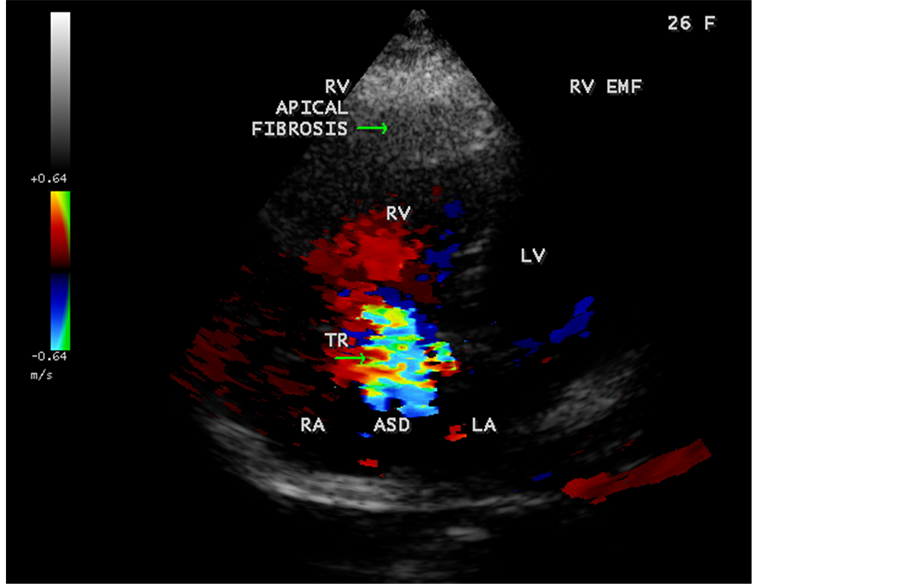

Figure 48. RV EMF with ASD showing tricuspid regurgitation in a 26-year-old female antenatally (Primi with 9 months amenorrhea).

A left ventricular EMF mimicking apical left ventricular hypertrophic cardiomyopathy as shown in Figure 23, Figure 24 and Figure 25 in a 2-year-old male child and an apical right ventricular hypertrophic cardiomyopathy in a 60-year-old female as shown in Figure 26 mimicking as right ventricular EMF had been found by Transthoracic echocardiographic screening. A right ventricular EMF associated with Psoriasis was shown in Figure 3 to Figure 7 in a 52-year-old male and a left ventricular EMF associated with pemphigus skin lesion in a 63-year-old male as in Figure 40 were detected in this region of Thoothukudi. RV EMF associated with congenital heart diseases such as ostium secundum atrial septal defect in a 26-year-old female antenatally (Primi with 9 months amenorrhea) as shown in Figure 49 and Figure 64 to Figure 66 in a 9-year- old girl. RV EMF associated with RV outflow tract disease (“Double chambered right

ventricle”) in a 16-year-old female as shown in Figure 50 to Figure 53 were detected. RV EMF with rheumatic involvement of mitral valve as shown in Figure 54 and Figure 55 in a 44-year-old female and in Figure 63 in a 55-year old female. Biatrial enlargement due to rheumatic atrioventricular (AV) valves (mitral and tricuspid) involvement characterized by stenosis of the valves are illustrated in Figure 56 to Figure 59 in a 54-year-old female and it is differentiated from EMF which is characterized by AV valve regurgitation as shown in Figure 34 and Figure 60. RV EMF associated with thickening and fibrosis of moderator band in a 16-year-old female was shown in Figure 46. RV EMF associated with apical left ventricular hypertrophic cardiomyopathy was shown in a 47-year-old male as in Figure 61 and in a 65-year-old female as in Figure 62.